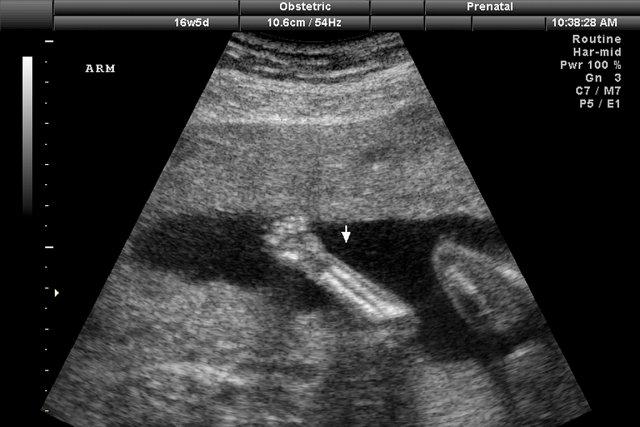

PHOTOTHÈQUE LA PRESSE